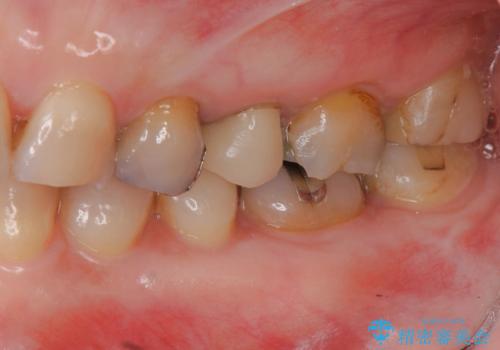

放置した虫歯 根管治療 フルジルコニアクラウン

- 虫歯治療を途中で中断し放置した歯の治療再開を希望され来院されました。

樹脂やクラウン・銀歯の老朽化がみられるため、丁寧に除去を行い根管治療を行ったのち、歯軋り・厚みの少なさを鑑みフルジルコニアクラウンによる補綴を計画します。